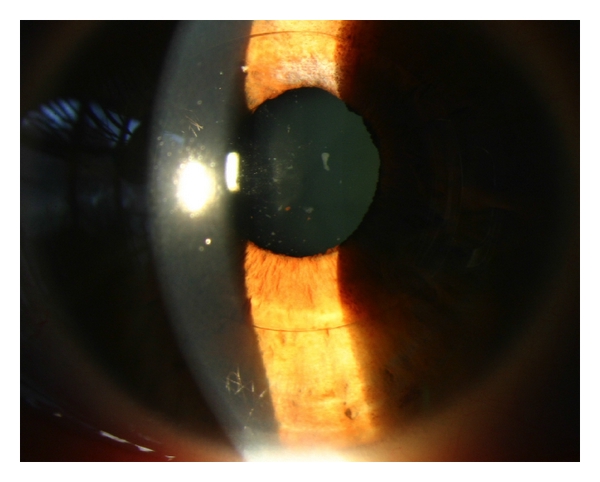

File:Iris claw AC inflammation.jpg

Iris_claw_AC_inflammation.jpg (600 × 482 pixels, file size: 126 KB, MIME type: image/jpeg)

Taneri et al. Creative Commons.

| current | 16:55, July 2, 2017 | 600 × 482 (126 KB) | Frank.S.Hwang (talk | contribs) | Chronic inflammation despite ongoing anti-inflammatory treatment two months postoperatively in an iris claw ACIOL [Digital image] by Taneri et al. Retrieved from https://www.hindawi.com/journals/joph/2014/923691/. Open access article. Licensed under CC... | |